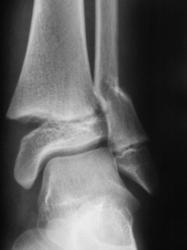

Пациент лечится в "другом лечебном учреждении", но снимки делает "по месту жительства", по направлению лечащего врача.

Мнения, как это довольно часто бывает, "разошлись". Хотелось - бы услышать Ваше мнение, как специалиста травматолога и мнения коллег по:

- процессу консолидации;

- удовлетворительности (неудовлетворительности) сопоставления костных отломков.

Продольная ось костьи нарушена, однако диастаз отломков незначительный, консолидация не выражена, но срастется обязательно, если не будет вторичного смещения.

Уважаемый OPEXOB прав, в данном случае имеет место вторичное смещение отломков, фиксация отломков проведенная этой методикой неадекватная. Видно, в какой то момент было захождение дистального отломка по длине, почему это произошло это уже момент случая, впринципе признаки консолидации умеренно выражены. Вот только одно Валентин Львович смущает есть критерии рентген-контроля которые указываются травматологом с целью отценки признаков консолидации и исключения вторичного смещения, этот случай видимо исключение.

Кстати уважаемый OPEXOB почему вас смутила данная методика, она вам известна, обычно фиксируют L- или Т- образными пластинами с винтами, просто в этом случае это более дешевле, т.е. с экономили.

На каком уровне ЦРБ/ГБ? Для ЦРБ может и сойти, для ГБ - сомнительно, такие переломы надо спец. пластинами с шурупами фиксировать. В общем не люкс, но результат можно считать приемлемым: стояние отломков удовлетворительное (небольшое захождение), формируется костная мозоль. Для полного счастья не хватает бокового снимка (хотя бы через грудную клетку, можно попытаться кассету под мышку засунуть, дополнительно луч скосить - перелом достаточно "низкий").

Методика остеосинтеза действительно не "общеупотребительна". Есть методика остеосинтеза проксимальных переломов плеча спицами, но там спицы несколько другие. Однако, как говорят, победителей не судят - стояние отломков для данного перелома вполне допустимое. Костная мозоль есть, перелом срастается. Всё должно быть хорошо.